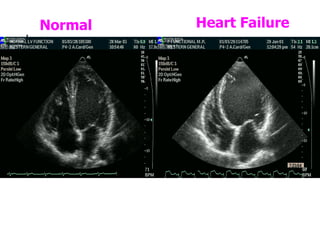

Normal Heart Failure